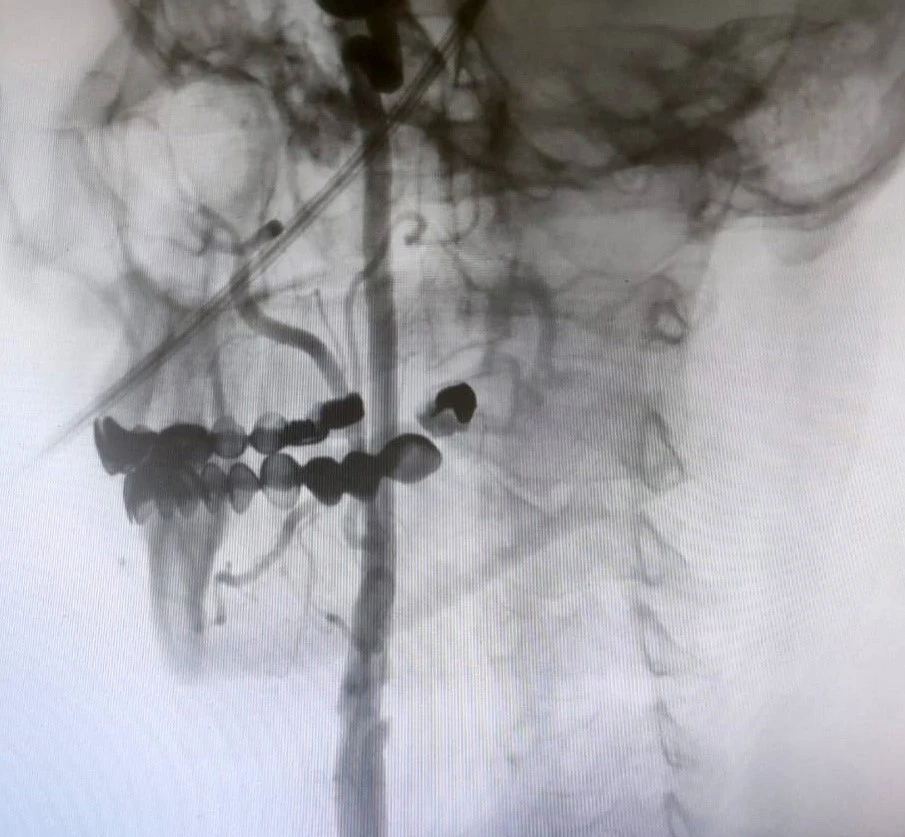

Manisa Şehir Hastanesi’nde girişimsel nöroloji ve girişimsel kardiyoloji uzmanlarının iş birliğiyle, beyni besleyen en büyük damarlar olan karotis (şah) damarlarındaki tıkanıklıklara karşı modern tedavi yöntemleri başarıyla uygulanıyor. Uzmanlar, bu damarlarda gelişen ciddi darlıkların inme (felç) riskini önemli ölçüde artırdığını belirtiyor. Bu nedenle, felç riskini azaltmak amacıyla hastalara stentleme işlemi uygulanıyor.

"Boyun damarlarını açma işlemi iki şekilde yapılabilir. Bir karotis endarterektomi dediğimiz ameliyatla bir diğer yöntem ise perkutan girişim dediğimiz stent yöntemiyle açılabilir. Biz kliniğimizde nöroloji ve kardiyoloji olarak bir konsey yapıyoruz. Damarı ciddi tıkalı olan ve buna bağlı felç geçirmiş hastalarda bu konseyde hastaya işlem yapıp yapmama kararı veriyoruz. Verdiğimiz karar çerçevesinde eğer hastaya işlem kararı vermişsek femoral arter dediğimiz kasık arterinden bir şitle 6 ya da 7 F çapında bir şitle ince bir boruyla bu damara giriş yapıyoruz ve boyun damarlarına ulaşıyoruz. Özellikle teller, filtreler ve stentlerle bu damarları açıp hastanın tedavisini gerçekleştiriyoruz. İşlem ameliyatsız olduğu için hastamız ertesi gün rahat bir şekilde problem olmazsa işlemde taburcu olabiliyor bu işlemden sonra. Bu işlemin yapılması için özellikle anjiografinin olduğu girişimsel nöroloji uzmanının ve girişimsel kardiyoloji uzmanının olduğu ve bu konuda yeterli vaka tecrübesine ve deneyime sahip uzmanların olduğu merkezler gerekir. Bunu yapabilmek için belli bir vaka sayısına ulaşmak ve bu konuda tecrübeli olmak gerekiyor. Biz de Manisa Şehir Hastanesi’ndeki girişimsel kardiyoloji ve nöroloji uzmanları olarak bu işlemi kliniğimizde efektif bir şekilde gerçekleştiriyoruz."